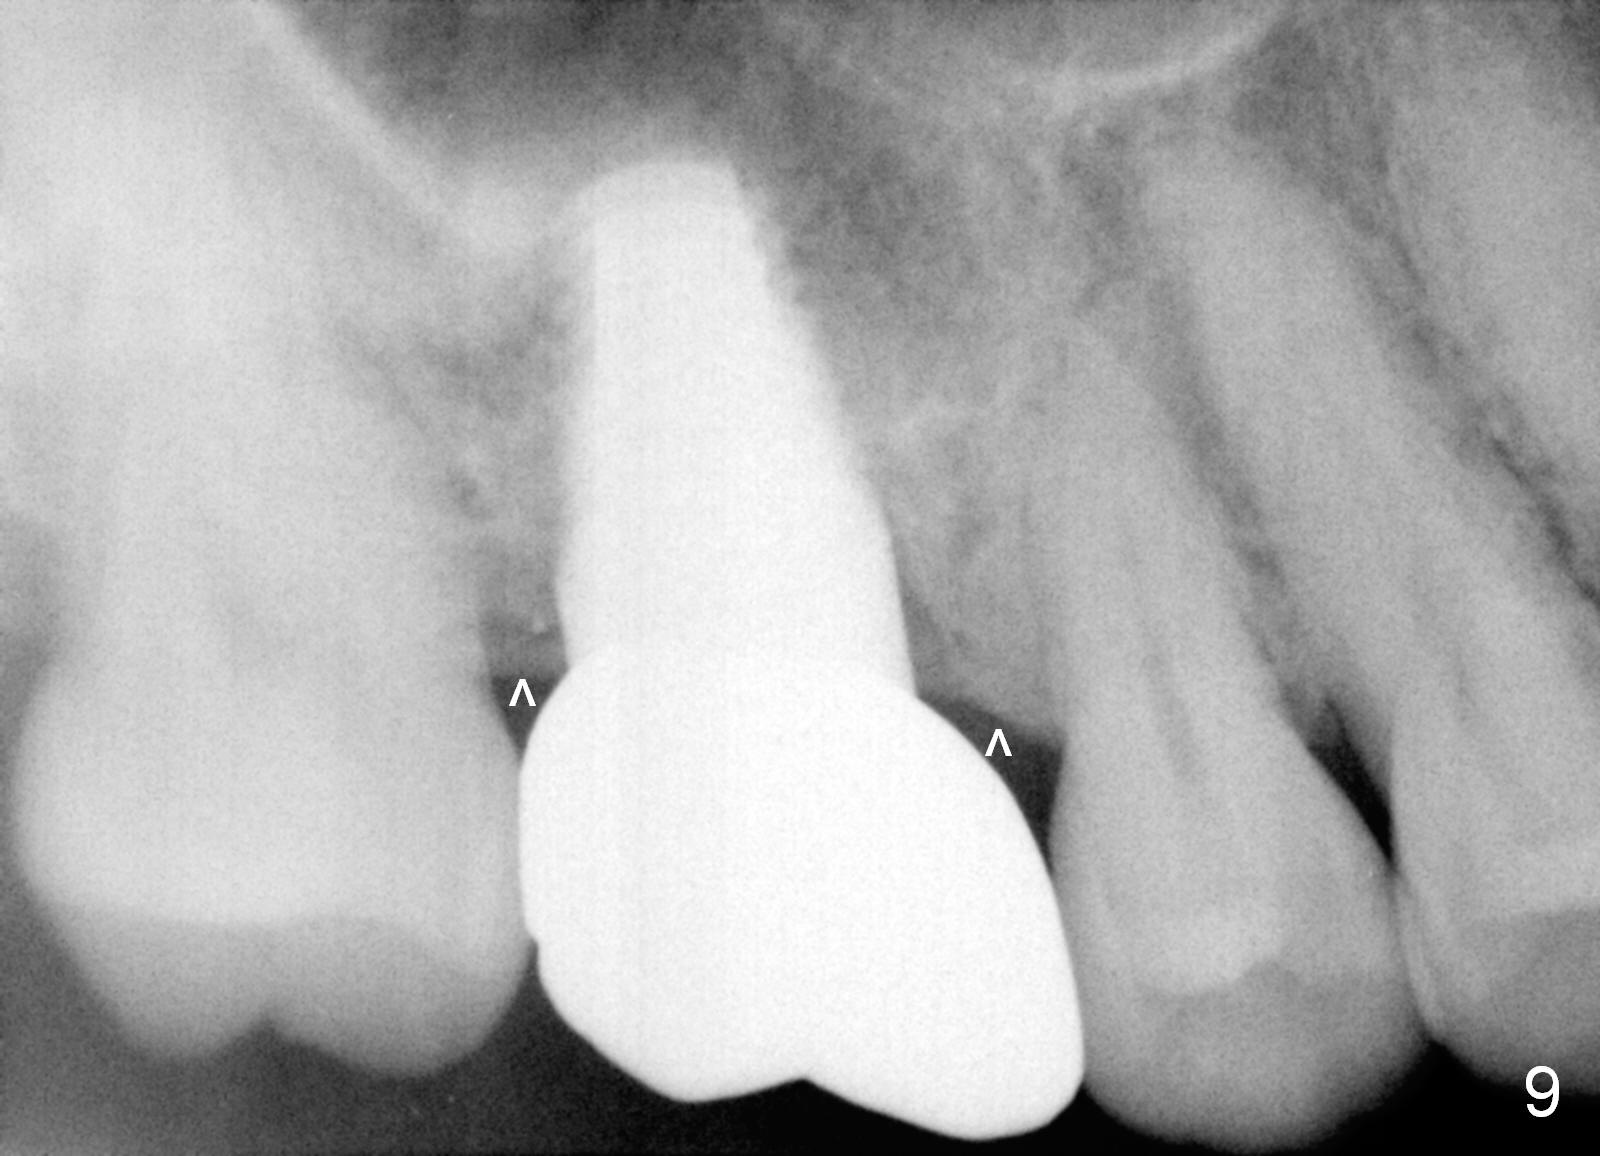

Our experience demonstrates higher failure rate associated with shorter implant in this situation. The depth of the osteotomy is then increased to 14 mm using the same series of osteotomes and taps. The bone at the top of the osteotomy finally wears off when the last tap is applied (7x17 mm). But the sinus membrane is intact. Osteogen is pushed into the osteotomy before placing a 7x14 mm implant with insertion torque > 60 Ncm (Fig.5). The implant contacts the gingiva tightly; no suture is necessary. There is no intra- or postop nasal hemorrhage. The wound heals 8 days postop (Fig.6). There is bone surrounding the apical portion of the implant in the sinus (Fig.7,8 *) 3.5 months postop. The implant is stable. There appears no crestal bone resorption 7.5 months post cementation (Fig.9 ^). Sinus lift is visible 16 months post cementation (Fig.10 (trimmed panoramic X-ray) arrowheads). There is discomfort between #2 and 3, probably due to poor oral hygiene. There is no deep pocket or bone loss (Fig.11, 26 months post cementation).